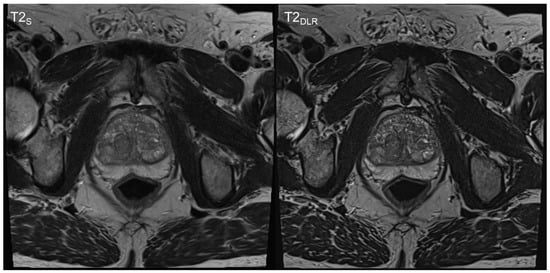

3. Results

3.1. Image Quality Analysis